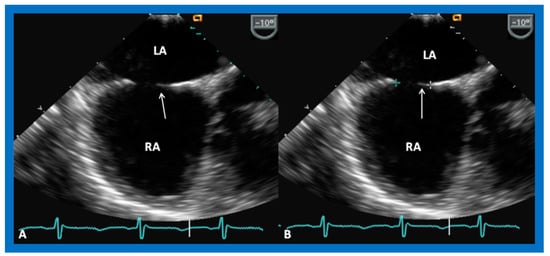

6. TEE and ICE

- Hellenbrand, W.E.; Fahey, J.T.; McGowan, F.X.; Weltin, G.G.; Kleinman, C.S. Transesophageal echocardiographic guidance of transcatheter closure of atrial septal defect. Am. J. Cardiol. 1990, 66, 207–213. [Google Scholar] [CrossRef]

- Singh, G.K.; Marino, C.; Rao, P.S. Ultrasound as an adjunct to cardiac intervention in the pediatric patient. J. Invasive Cardiol. 1996, 8, 341–349. [Google Scholar] [PubMed]

- Hijazi, Z.M.; Wang, Z.; Cao, Q.L.; Koenig, P.; Waight, D.; Lang, R. Transcatheter closure of atrial septal defects and patent foramen ovale under intracardiac echocardiographic guidance: Feasibility and comparison with transesophageal echocardiography. Cath. Cardiovasc. Interv. 2001, 52, 194–199. [Google Scholar] [CrossRef]